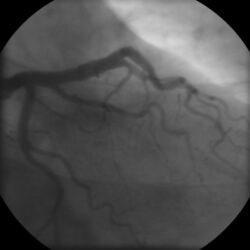

Coronary angiogram of a male

Coronary angiogram of a female